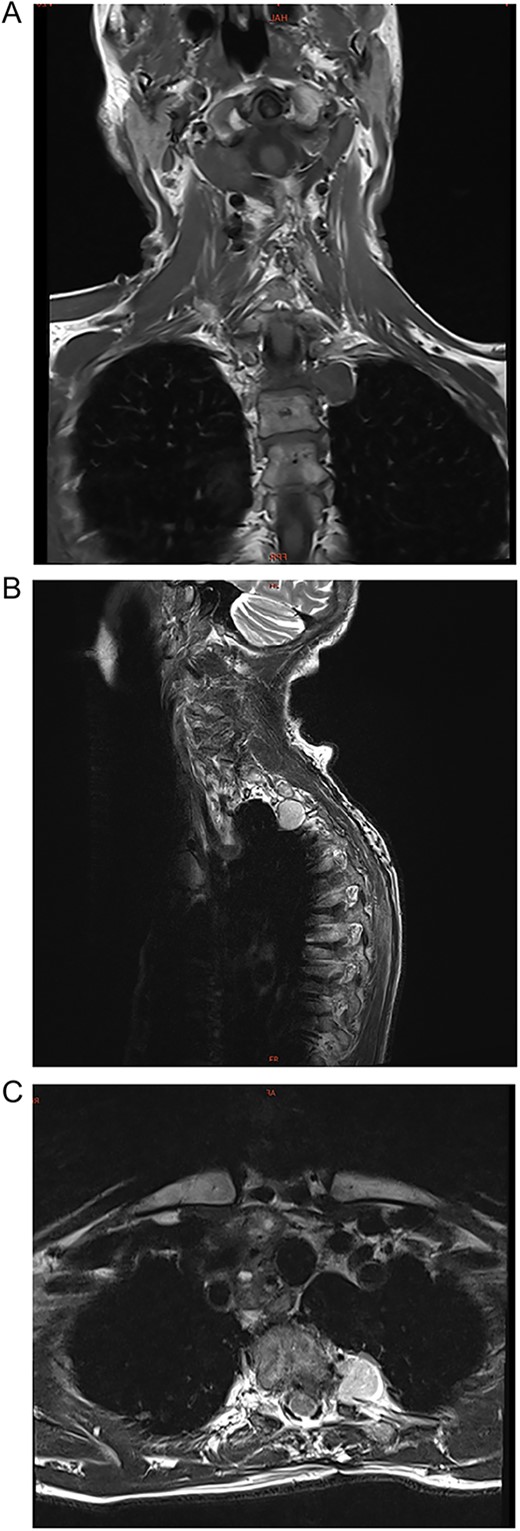

A 72-year-old female presented to neurology with a 2-year history of progressive pain in the upper thoracic spine. The pain radiated to her left arm and leg. She was non-responsive to pain relief but had no functional deficits. Her only relevant past medical history was multi-segmental degenerative changes in the lumbar and cervical spine. She took no known medications. A physical examination revealed pain in the upper thoracic spine with no other findings. Her routine blood examination was unremarkable. Chest magnetic resonance imaging (MRI) revealed a 2.7 × 2.0 × 1.2 cm para-vertebral mass in the left hemithorax at the thoracic vertebrae T2/T3 (Fig. 1). It extended into the foramina and had extensive dural sac contact. It had smooth contours with no bony destruction.

(A–C) Coronal, sagittal, and axial images of a 2.7 × 2.0 × 1.2 cm para-vertebral mass in the left hemithorax at the thoracic vertebrae T2/T3 level.